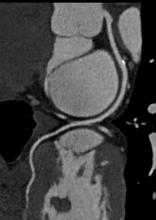

Coronary computed tomography angiography (CCTA) is a noninvasive tool that can be used for identifying myocardial ischemia and coronary artery plaques. It acts as a proven prognostic/diagnostic tool for patients who are asymptomatic as well as in the mild- to medium-risk spectrum of coronary artery disease (CAD).

There are currently three major trends in cardiovascular computed tomography (CT) technology — lowering radiation dose, development of myocardial perfusion imaging and the use of CT datasets for procedural planning, especially for transcatheter aortic valve replacement (TAVR).